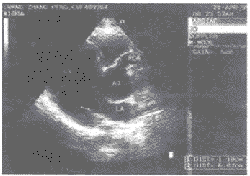

超聲心動圖:二維超聲心動圖可直接顯示擴大的冠狀動脈,也可進一步證實特異性的心腔擴大。某些情況下,二維超聲和都卜勒超聲心動圖可發現冠狀動脈瘺。

超聲心動圖術前超聲心動圖檢查可見病變之冠狀動脈擴張及局部動脈瘤形成,有時可見瘺孔的位置,因此術前對可疑病例應進行詳細的超聲檢查。